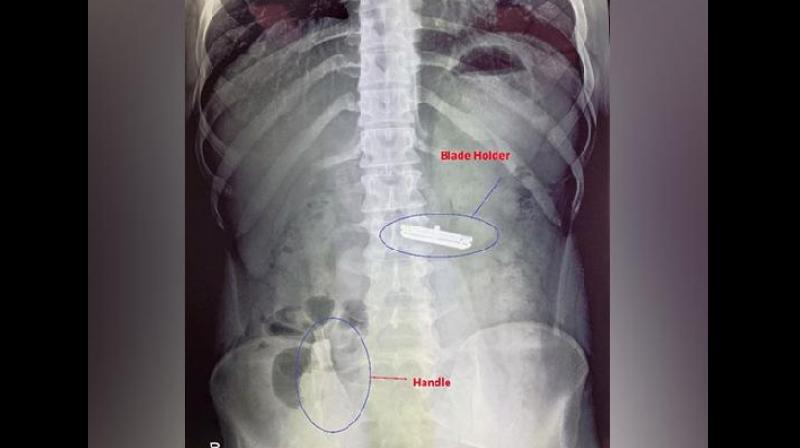

The razor was ingested in two parts: the blade holder, which became lodged in the stomach, and the handle, which traveled to the large intestine. The situation posed a serious threat to the young man’s life.

• Step 1: A laparotomy was performed to open the stomach and remove the blade holder.

• Step 2: The handle, which had reached the colon, was carefully milked distally and removed using sigmoidoscopy.